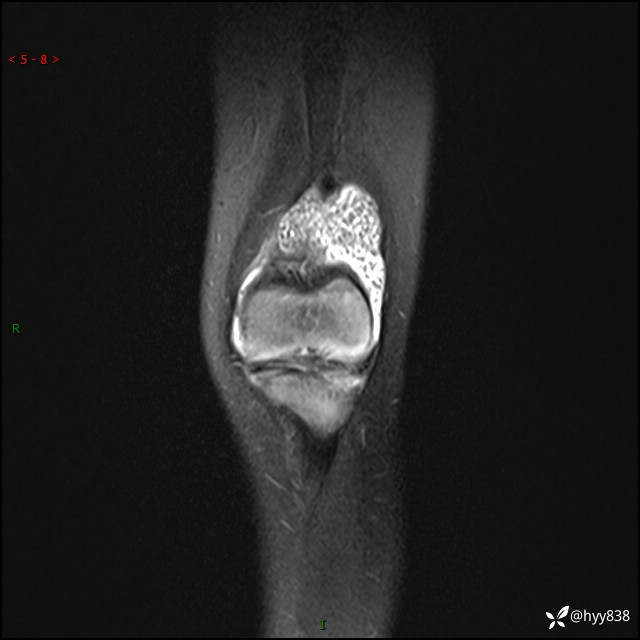

现病史:患儿1月前无明显诱因出现左下肢跛行,伴左膝关节红肿,无发热、咳嗽、恶心、呕吐等症,于当地医院就诊行X线片未提示异常,今至我院门诊就诊,门诊医师拟“跛行待查”收入院。 病后,患儿精神、食欲可,睡眠欠安,大小便通畅,体力体重无明显下降。

左膝MRI平扫